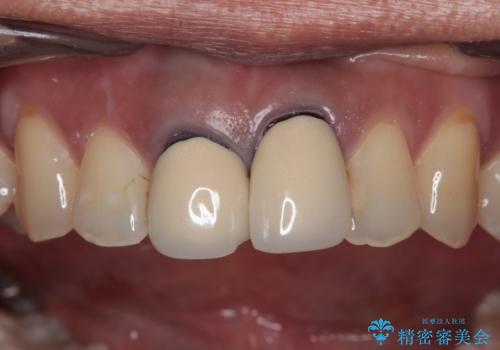

- 前歯のクラウン付近の歯肉が黒く見えることを気にして来院された患者様です。

10年以上前に根管治療を行っており、その際にはラバーダムを使用してしっかりと治療を行っていたとのことで、今回は根管治療は行わずに土台のみを作り替えた上で、オールセラミッククラウンにて補綴治療を行うこととしました。